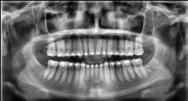

Panorámicas de inicio a fin (Figura 16) el paralelismo radicular, genera estabilidad a largo plazo en el tratamiento. Se extrajeron los terceros molares para eliminar discrepancia posterior y lograr adecuada

Figura 16. Radiografías panorámicas. a) Inicio. b) Progreso. c) Final.

distalización. Se alineo la curva de Spee acetuada y se libero correctamente el apiñamiento dental que presentaba el paciente al inicio del tratamiento.

1-PLT de 129º e IMPA 99º proinclinación de incisivos tanto superiores como inferiores. En la radiografía panorámica (Figura 7), la presencia de 32 órganos dentarios, con terceros molares inferiores aún sin erupcionar y terceros molares superiores

ya erupcionados, falta de paralelismo radicular, asimetría condilar, articulación temporomandibular (ATM) izquierda afectada.